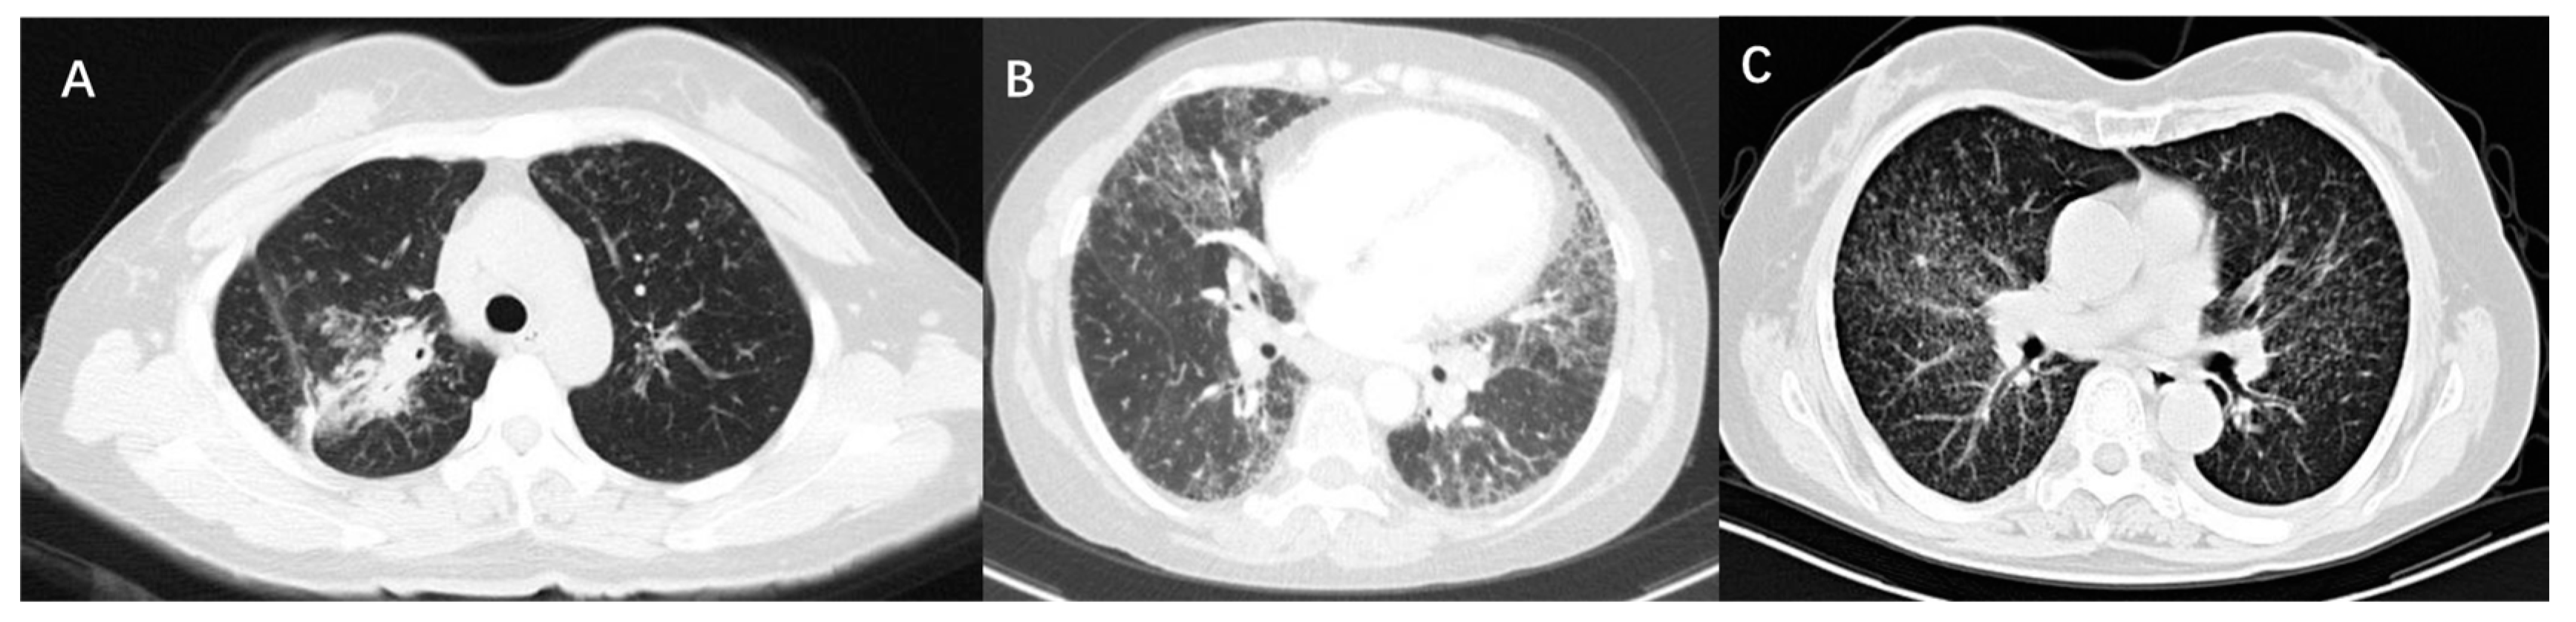

High-resolution computed tomography (HRCT) is an accurate modality to identify mediastinal lymphadenopathy and subtle pulmonary parenchymal changes. In clinical practice, it is widely used for the initial evaluation of sarcoidosis and monitoring of disease progression. Compared with CXR stages, HRCT findings of sarcoidosis have a better correlation with the severity of PFT changes [23,28]. PFT parameters were negatively correlated with CT scores of consolidation pattern and ground-glass opacities. There were obvious correlations between lung consolidation imaging scores and FVC, FEV1, and FEV1/FVC, while the ground-glass opacity scores were significantly related to DLCO [22,29]. As for micronodules, whether lung function is affected depends on the amount of micronodules and the extent of lung involvement. It was suggested that the higher the number of micronodules is, the lower the spirometric values are [29]. If micronodule patterns occur in a very limited lung area, PFT parameters will not be affected [22]. The main CT features of pulmonary fibrosis included honeycombing patterns, diffuse linear patterns, and bronchial distortion. Honeycombing patterns are usually associated with restrictive dysfunction and decreased DLCO. Patients with bronchial distortion often experience a lower FEV1 and FEV1/FVC. Linear patterns generally only cause slight functional damage [28]. Figure 1 shows the CT images of three sarcoidosis patients with different pulmonary dysfunctions.

Figure 1.

CT images of three patients with sarcoidosis. (A) Shows consolidation on CT scan and the PFT is characterized by restrictive ventilation dysfunction, with an FVC of 67.9% predicted and FEV1 of 61% predicted. (B) Shows fibrosis and bronchial distortion on CT scan and the PFT is characterized by restrictive ventilation dysfunction and decreased diffusion function, with an FVC of 44.4% predicted, FEV1 of 52.0% predicted, and DLCO of 50.9% predicted. (C) Shows multiple micronodules on CT scan and the PFT is characterized by mixed ventilation dysfunction, with an FVC of 71.3% predicted, FEV1 of 62.3% predicted, FEV1/FVC of 69.46%, and normal DLCO.